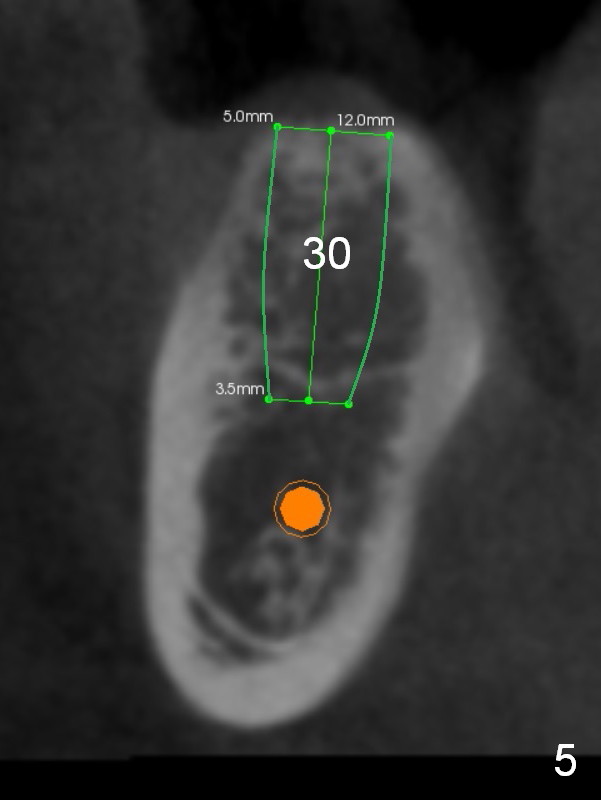

A coronal section at the site of #30 confirms that a 12 mm implant is safe (Fig.5).

Initial height at #30 and 31 will be 12 and 8 mm after infiltration anesthesia. Osteotomy at #31 is proceeded cautiously. If the 1st intraop PA confirms depth safety margin, depth will be 2 mm more than implant length so that the implant will be placed lower.